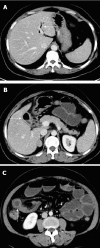

Gallstone ileus (GI) is characterized by occlusion of the intestinal lumen as a result of one or more gallstones. GI is a rare complication of gallstones that occurs in 1%-4% of all cases of bowel obstruction. The mortality associated with GI ranges between 12% and 27%. Classical findings on plain abdominal radiography include: (1) pneumobilia; (2) intestinal obstruction; (3) an aberrantly located gallstone; and (4) change of location of a previously observed stone. The optimal management of acute GI is controversial and can be: (1) enterotomy with stone extraction alone; (2) enterotomy, stone extraction, cholecystectomy and fistula closure; (3) bowel resection alone; and (4) bowel resection with fistula closure. We describe a case to highlight some of the pertinent issues involved in GI management, and propose a scheme to minimize recurrent disease and postoperative complications. We conclude that GI is a rare condition affecting mainly the older population with a female predominance. The advent of computed tomography and magnetic resonance imaging has made it easier to diagnose GI. Enterotomy with stone extraction alone remains the most common surgical method because of its low incidence of complications.